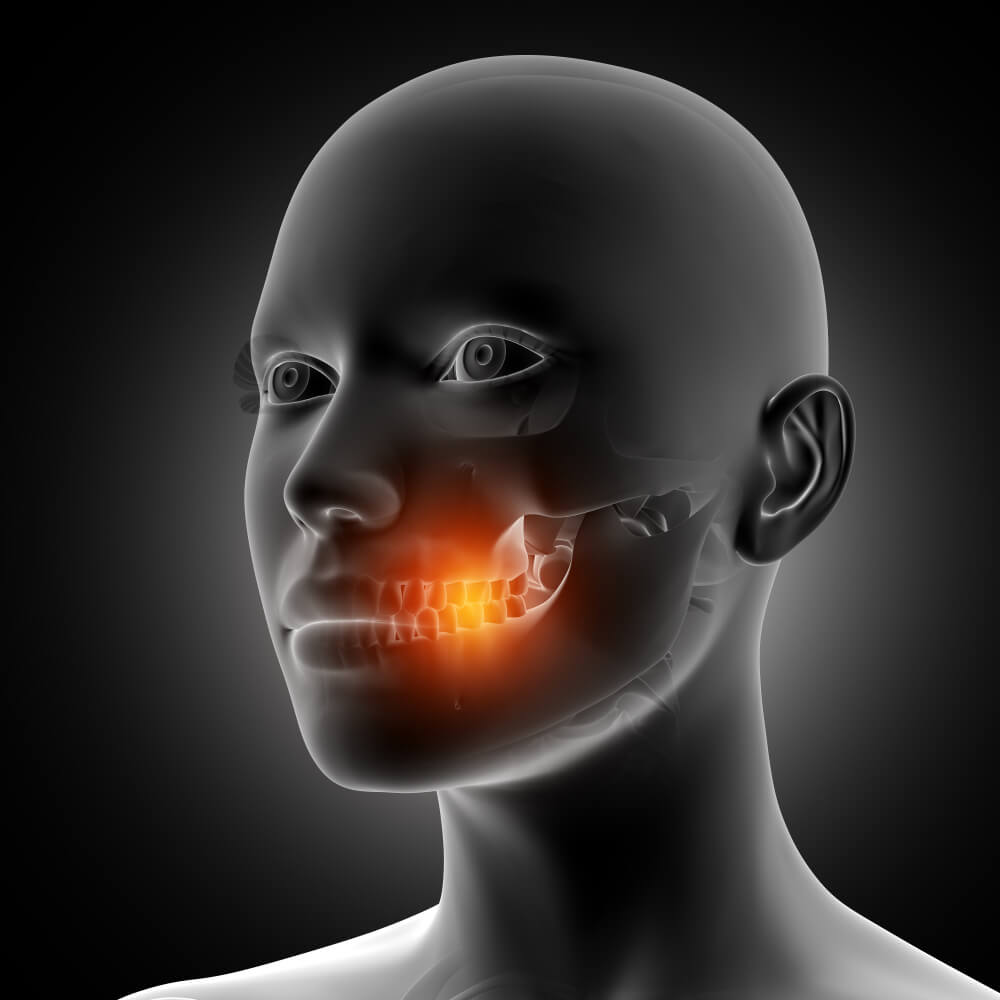

Gum disease is common and uncomfortable, but increasing research suggests it may also be connected to a number of unexpected health conditions. Looking after your teeth could therefore be more important than many people realise. Plaque — a sticky film containing bacteria — gradually forms on teeth. If it is not removed through brushing, these bacteria can begin to irritate the gums.

As irritation develops, the gums may become red, tender, or swollen; this early stage is known as gingivitis. In many cases, gum disease can be controlled or avoided through consistent oral hygiene. However, if it progresses further, it may lead to periodontitis, a more serious condition that damages the structures supporting the teeth.

Gum disease, also referred to as periodontal disease, is very common. According to the Centers for Disease Control and Prevention (CDC), nearly half of adults in the United States experience some form of gum disease.

Researchers already understand many of the biological processes involved in periodontal disease, and newer studies indicate that it could also be linked to several other health conditions, including Alzheimer’s disease, certain cancers, and respiratory illnesses. In this overview, we explore some of the surprising associations between gum disease and wider health concerns.